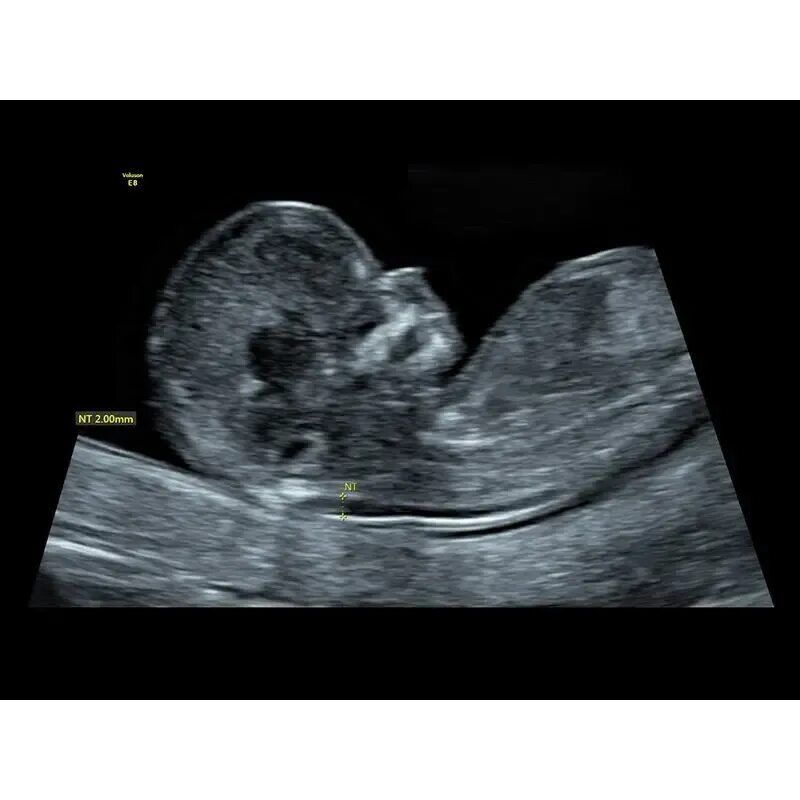

Воротниковая пространство форум